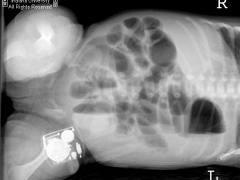

正常新生儿多在出生12h内初次排出胎粪,或可延至12~24h,极少数在24~48h才开始排便。若新生儿因胎粪稠厚、积聚在乙状结肠及直肠内,出生48h后尚未开始排便,出现一过性低位肠梗阻症状,称胎粪性便秘。新生儿胎粪性便秘是由于胎粪稠厚积聚在乙状结肠及直肠内,排出量很少,于出生后72小时尚未排完胎粪,表现为低位肠梗阻症状,如腹胀、拒奶,有时呕吐,腹部X线片显示小肠和结肠充气,或有胎粪颗粒影,肛门指检可触到秘结的胎粪,并可随手指带出胎粪,有时可使症状缓解,如胎粪不能顺利排出,可用等渗温盐水灌肠,每次15~30ml。也可用开塞露灌肠,每次5ml,大量胎粪排出后症状消失,不再复发。